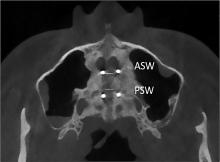

Objective To analyze the clinical outcome of microimplant screw-assisted maxillary rapid arch expansion in patients with Class Ⅲ malocclusion. Methods A total of 58 patients with Class Ⅲ malocclusion treated at Handan Stomatological Hospital from January 2022 to April 2023 were selected as the control group, and surgically assisted rapid maxillary arch expansion treatment was used. A total of 58 patients with Class Ⅲ malocclusion treated at Handan Stomatological Hospital from June 2023 to May 2024 were selected as the observation group, and micro-implant assisted rapid maxillary arch expansion treatment was performed. After 3 months of treatment, cone beam CT was taken to compare the bone structure, soft tissue measurement results, occlusal function, arch expansion effect, and postoperative complications between the two groups of patients before and after treatment. Results The bony width and the tilt of the supported teeth of the maxillary teeth increased in both groups after treatment, compared with the preoperative period(P<0.05). The nasal width of the maxillary first molar in the observation group increased significantly, and the tilt of the supported teeth were all reduced significantly compared with the control group(P<0.05). After treatment, ANB and LI-MP of the observation group were higher than those of the control group; SNB and MP-SN were lower than those of the control group. Facial convexity angle and nasolabial angle were higher than those of the control group; chin-labial angle was lower than those of the control group, and occlusal function was higher than those of the control group(P<0.05). The postoperative complication rate of 1.72% in the observation group was lower than that of 13.79% in the control group, with a significant difference(P<0.05). Conclusion Micro-implant-assisted rapid maxillary arch expansion can achieve obvious bony expansion effect, promote the improvement of the patient’s bony structure, improve their facial morphology, and enhance their occlusal function, which can be promoted and applied.